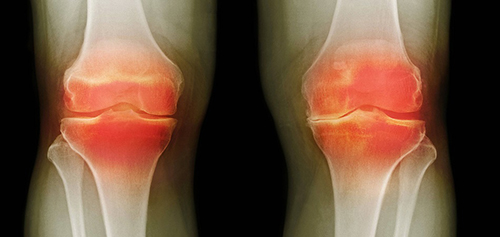

สาเหตุหลักของโรคข้อ คือการตกตะกอนของผลึกเกลือในข้อ เนื่องจากระบบไหลเวียนโลหิตและของเหลวไขข้อ (synovial fluid) เสื่อมลง:

- กรดยูริก (Urate crystals) ทำให้เกิดโรคเกาต์

- แคลเซียมเกาะกระดูก (Osteophytes) คือตัวการของโรคข้อและกระดูกกว่า 97% เช่น โรคข้ออักเสบ โรคข้อเสื่อม โรคกระดูกอ่อน โรคกระดูกพรุน โรคไขข้ออักเสบ โรคถุงน้ำในข้ออักเสบ และแม้แต่ซีสต์ของปมประสาท

เมื่อเกลือเหล่านี้เกาะอยู่บนพื้นผิวของข้อต่อ คราบเกลือเหล่านี้เหมือนกระดาษทรายที่ทำลายเนื้อเยื่อรอบโดยรอบ กระดูก และกระดูกอ่อน เมื่อผลึกโตขึ้น เกลือจะเริ่มทำลายเนื้อเยื่อของกล้ามเนื้อ เอ็น หลอดเลือด และเส้นเลือดฝอย ทำให้เกิดการอักเสบ ติดเชื้อ บวม ก่อให้เกิดการอักเสบและปวดอย่างรุนแรง

ในกรณีรุนแรง การสะสมเกลือจำนวนมากอาจทำให้กระดูกหักได้ง่ายเมื่อมีการเคลื่อนไหวอย่างกะทันหัน ส่งผลให้พิการและข้อต่อไม่สามารถเคลื่อนไหวได้